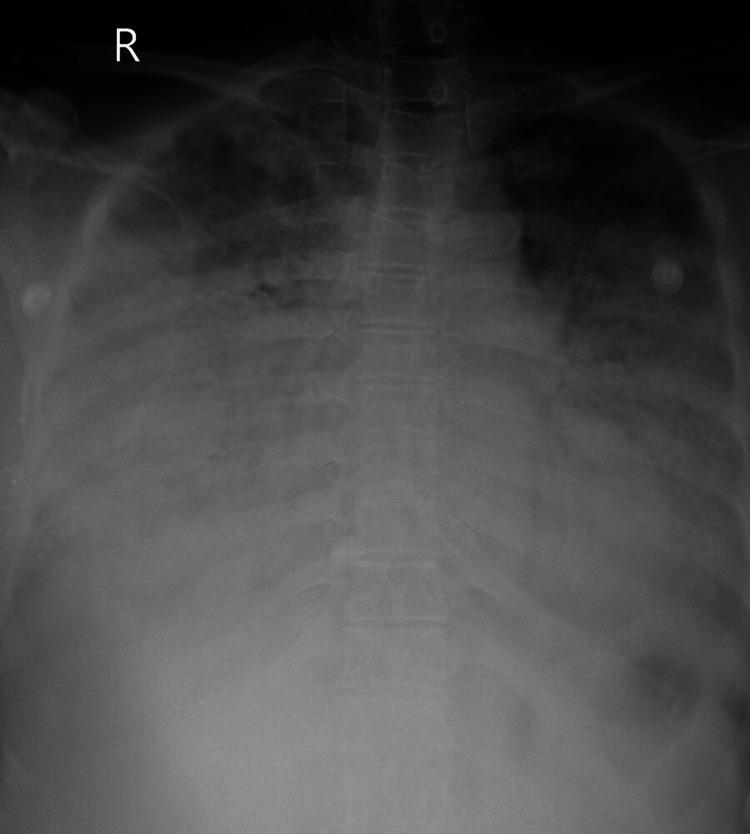

Chemical pneumonitis caused by dimethanol and glutaraldehyde exposure is a serious medical condition that requires prompt and effective treatment. As per a literature search in Google Scholar, PubMed, and Scopus, this is the first instance of chemical pneumonitis caused after fumigation with dimethanol and glutaraldehyde inhalation. This article discusses the factors that can contribute to the development of chemical pneumonitis and outlines the diagnostic and treatment options available to healthcare professionals. By understanding the causes and consequences of dimethanol- and glutaraldehyde-induced chemical pneumonitis, medical professionals can provide better care to their patients and help prevent future cases of this potentially life-threatening condition. This describes a case of a 60-year-old female who presented to the emergency department complaining of acute onset of shortness of breath approximately 48 hours after being exposed to dimethanol and glutaraldehyde while working in intensive care. After 13 days, the patient's symptoms subsided and she was discharged. On follow-up, after 1 month, there was a marked resolution of the initial symptoms.

接触二甲醇和戊二醛引起的化学性肺炎是一种严重的病症,需要及时有效的治疗。根据在谷歌学术、PubMed和Scopus上的文献检索,这是首次因吸入二甲醇和戊二醛熏蒸后引发化学性肺炎的案例。本文讨论了可能导致化学性肺炎发生的因素,并概述了医疗专业人员可用的诊断和治疗方案。通过了解二甲醇和戊二醛引起的化学性肺炎的病因和后果,医学专业人员可以为患者提供更好的护理,并有助于预防这种潜在的危及生命病症的未来病例。本文描述了一名60岁女性的病例,她在重症监护病房工作时接触二甲醇和戊二醛后约48小时出现急性呼吸急促,前往急诊科就诊。13天后,患者症状消退并出院。在1个月后的随访中,初始症状明显缓解。